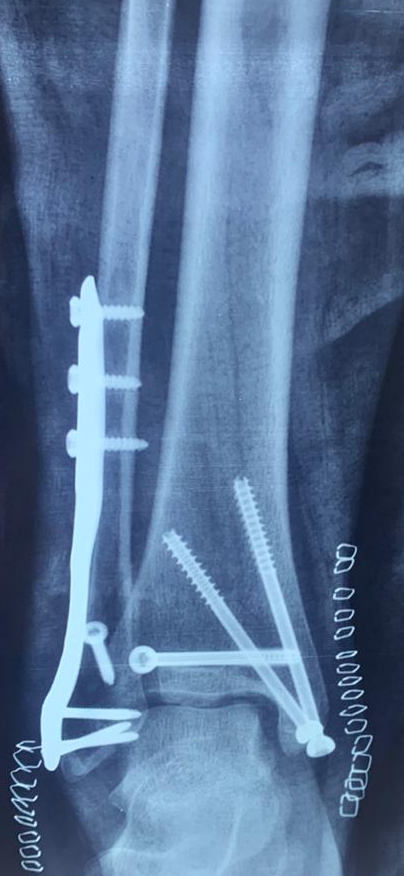

PROFILE TRAINING AND PRESENTATION Dr. Niranjanan Recieving Diploma SICOT degree in Rome, Italy Dr. Niranjanan being awarded fellowship certificate at Indian spinal injuries centre CLIINIC SOME OF Dr. NIRANJANAN's CASES